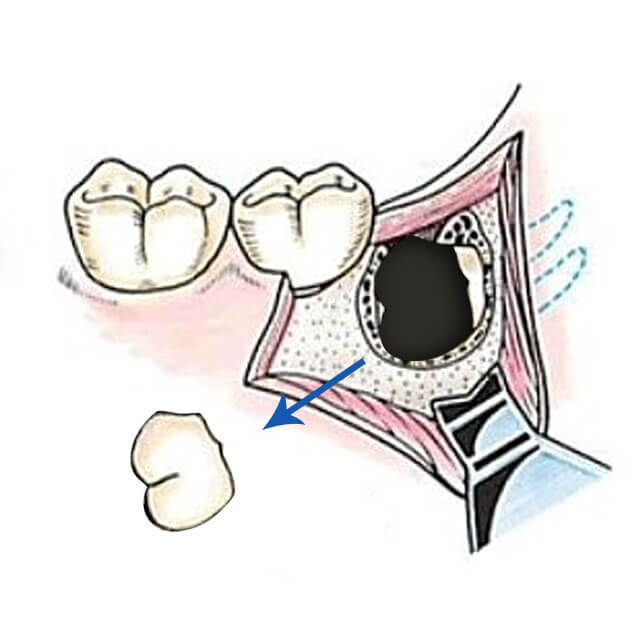

4,親知らずの周りの骨を削り、歯の歯冠部分を露出させます。

5,埋伏歯の歯冠をタービンで分割し除去します。

6,残った歯根部分を抜歯します。歯根が2本以上あって大きく曲がっていたり、歯根が肥大していたり、骨と癒着していて、そのままでは抜歯できない場合は歯根を分割したり、歯根周囲の骨を削ったりして抜歯します。

7,抜歯部を生理食塩水にて入念に洗浄します。

8,切開した粘膜を縫い合わせます。骨内の血管からの主家kつが止まりにくい場合や内科治療上の内服薬などで抜歯した部分に止血剤を使用します。

9,縫合した場合は抜歯後約1週間で抜糸します。

イラストの出典「抜歯の臨床」医歯薬出版